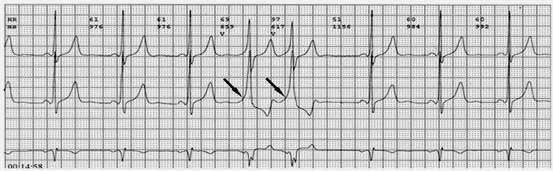

2.心電圖表現(xiàn):典型預(yù)激表現(xiàn)為竇性搏動的PR間期<0.12秒,某些導(dǎo)聯(lián)的QRS波時限>0.12秒,QRS波起始部粗鈍(稱delta波),ST段有繼發(fā)改變,T波與主波相反。